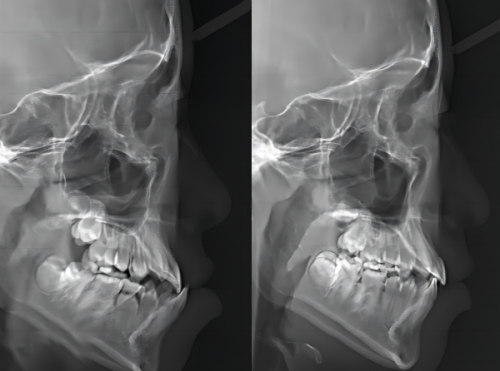

医院配备了一系列精良的医疗设备,如高频电刀、根管填充器、CBCT机、数字化口腔全景机、数字化口腔内窥镜、CBCT口腔全景检查设备、数字导板、数字化正畸设备等。 这些设备的应用,能够确保口腔疾病的诊断更加正确,治疗更加科学、精细。

在种植牙领域,合肥中诺口腔医院采用了北京3级中诺口腔医院研发的“立得用即刻种植”技术。 技术通过数字化3D技术实现种植手术的可视化、精控化,术前能够提前定位好种植体的植入位置、方向、深度等,轻松避开神经、血管等敏感区域,减少术中出血和并发症的风险。同时,该技术还独特地将植体呈“W”状植入牙槽骨,使植体更加稳固,手术耗时短且种植牙的使用寿命更长。